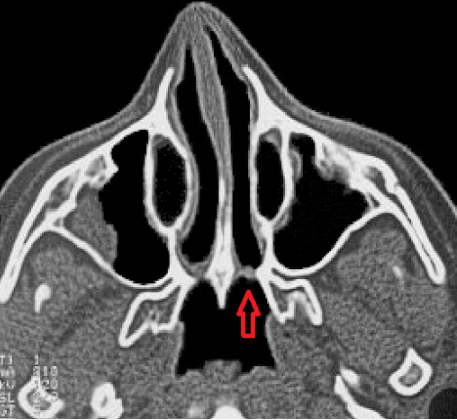

Placa atrésica em coanas. Atresia de coanas bilateral. Fonte: https://www.researchgate.net/figure/Axial-CT-scanof-a-bilateral-mixed-bony-membranous-choanal-atresia_ fig2_267702418